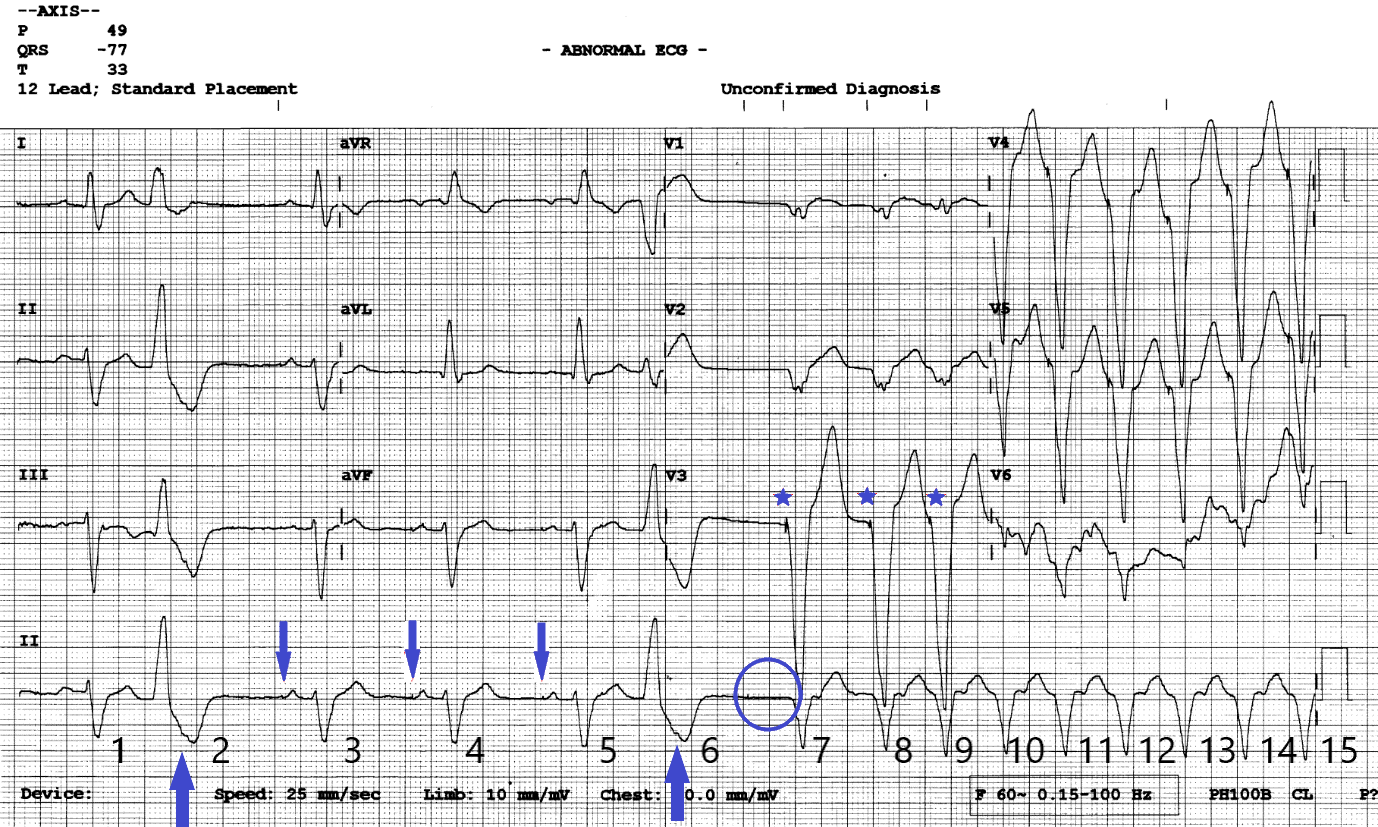

Figure 2

12 lead ECG with annotations. Blue down arrows show subtle atrial pacing artefacts. Blue up arrows show retrograde P waves in the ST segment of the PVC’s. Blue stars show ventricular pacing artefacts. The blue circle shows where an expected AP impulse should have been delivered.

The answer is pacemaker malfunction with the ECG capturing the onset of a pacemaker mediated tachycardia (PMT) triggered by loss of atrial capture. Non-sustained VT and SVT with BBB can be ruled out as broad complex beats have pacing spikes preceding each QRS (blue stars) indicating ventricular pacing. PVC’s set up the circumstance for PMT creating a compensatory pause and bringing in atrial pacing but are not directly responsible for the episodes. The episodes are not associated with physical activity and show sudden onset of paced tachycardia which is not typical for rate responsive pacing behaviour.

ECG Review

The ECG starts with (1) an atrial sensed ventricular sensed event (AS/VS). Note the round shaped sinus P wave and no pacing artefact preceding the P wave or QRS complex. The next event (2) is a PVC which has a subtle retrograde P wave (1st blue up arrow) within the ST segment. This suggests the presence of VA conduction however here the retrograde P wave falls in the post ventricular atrial refractory period (PVARP) and does not affect pacemaker timing intervals. The lower rate interval (60 bpm) times out and the next event (3) is an atrial paced beat which has good AV conduction (AP/VS). There is a subtle atrial pacing artefact (1st blue down arrow) preceding the P wave and a slightly peaked paced P wave morphology which is different to the previous sinus sensed P wave. The next two events (4&5) are AP/VS events at the lower rate interval of 60 bpm. Event (6) is another PVC. After this PVC the lower rate interval times out again, but this time there is no paced or sensed atrial event (blue circle). Event (7) is a ventricular paced (VP) complex with a clear pacing artefact preceding the QRS (1st blue star) which is followed by 8 further ventricular paced beats (8-15) occurring at the upper rate limits of 130 bpm.

The sequence is typical of a pacemaker mediated tachycardia initiated by a loss of AV synchrony which in this case is due to loss of atrial capture. It is a rhythm which requires intact VA conduction and occurs when a ventricular paced event or PVC conducts back to the atria giving rise to a retrograde P wave which falls outside of the programmed PVARP. The retrograde P wave is sensed as an atrial event which triggers an AV interval. When the AV interval times out a ventricular paced beat is delivered and the sequence repeats until there is loss of atrial sensing, loss of retrograde conduction or a PMT prevention algorithm is activated.

In the acute setting a paced broad complex tachycardia at rest at the upper tracking rate most commonly 120/130 bpm should raise suspicion of a PMT. Other differentials include tracking of sinus or atrial tachycardia, inappropriate rate response behaviour, failure to mode switch or inappropriate programming of a device algorithm.